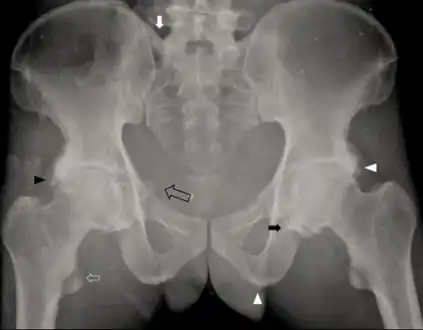

a-c)Brain computed tomography shows diffuse symmetric parenchymal calcifications -

Individual with idiopathic hypoparathyroidism-diffuse osteosclerosis, capsular ossification around bilateral hip joints arrow, ossification of bilateral iliolumbar ligaments arrow, irregular bony excrescences arrowhead, subtle calcification of the right sacrospinous ligament open arrow